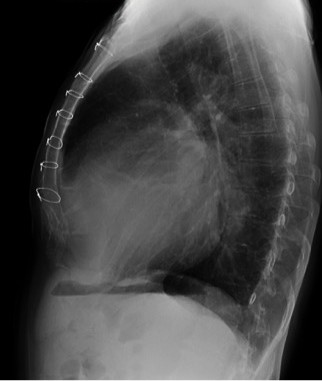

CASO: Febrícula y tos de 4 días de evolución.

Hallazgos:

- En la placa PA se observa una asimetría en los hilios pulmonares, el hilio izquierdo tiene una densidad aumentada.

- Tras examinar la placa lateral se observa un aumento de densidad en la columna que puede ser compatible con una condensación, es el signo de la desnificación vertebral.

SIGNO DE LA DENSIFICACIÓN VERTEBRAL: En la radiografía lateral normal, la densidad de la columna torácica tiende a disminuir desde la parte superior hasta el diafragma; la alteración de ese patrón por la presencia de una densidad superpuesta a la columna, indica la existencia de una consolidación pulmonar. Este signo adquiere especial valor cuando en la proyección posteroanterior la consolidación está oculta en el espacio retrocardíaco o en la base pulmonar.